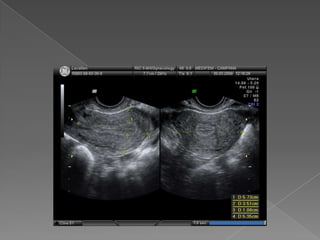

 Visibles acada lado del útero  Reparo: vasos ilíacos  Móviles, posición variable  Estructuras ovoideas , hipoecogénicas, porción central mas ecogénica  Tamaño : 3 cm x 2 cm x 2cm  Volumen : L x AP x T x 0.523  Vol. : 6 a 10 cm cúbicos , max :14 -16  Folículos : fácil identificación  Miden de 2 a 25 mm de diámetro